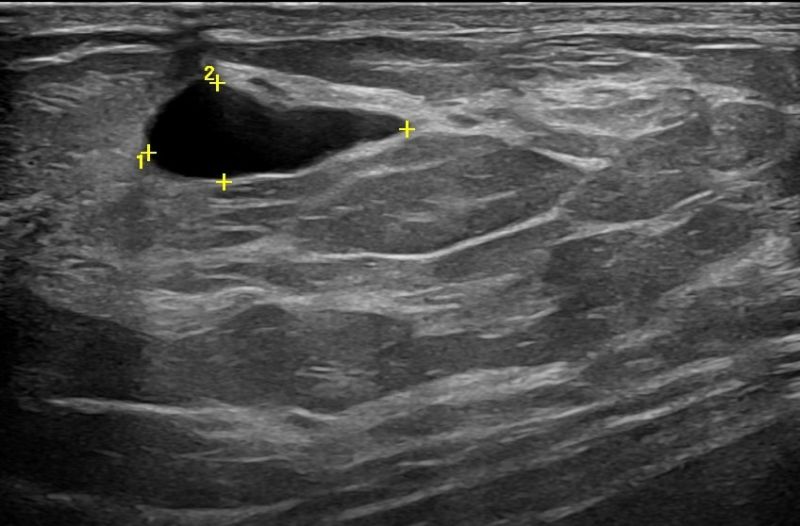

Modern ultrasound machines, equipped with advanced high-frequency transducers, techniques such as Color Doppler, Power Doppler, B-Flow, and Elastography, allow the analysis of breast architecture with exceptional accuracy.

Elastography can highlight the elasticity of a lesion, indicating whether it is hard or soft. Through this technique, we can assess the nature of the lesion, providing indications of whether it is benign or malignant. Additionally, with the contribution of Color Power Doppler and B-Flow, we can monitor the vascular flow within the lesions, offering even more information about the type and nature of the abnormality.

In addition to breast examination, Breast Ultrasound also includes the examination of the axillary regions. Through this process, we detect any presence of lymph nodes, and with the help of Elastography, we can evaluate them.